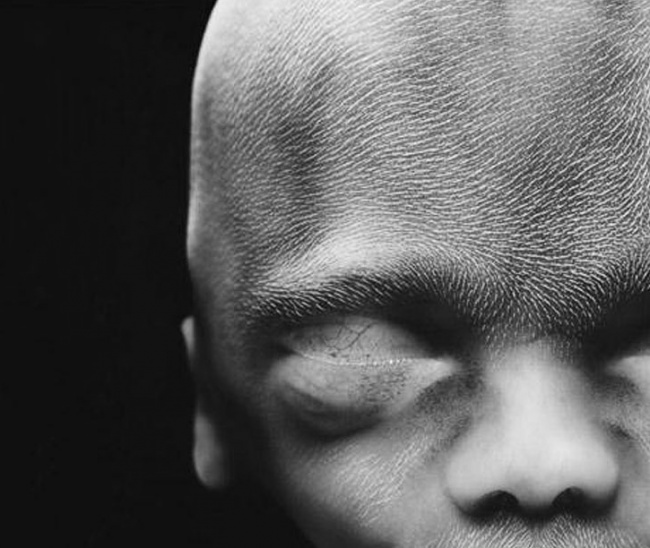

A 10. héten a szemhéjak már félig zárva vannak. Pár nap és teljesen lefedik a szemet.

16 hetesen.

A csontváz kialakulóban van, ilyenkor még rugalmas. A vékony bőr miatt látható az érhálózat.

A 18. héten a magzat már kb. 14 cm és érzékeli a külvilágból érkező hangokat.